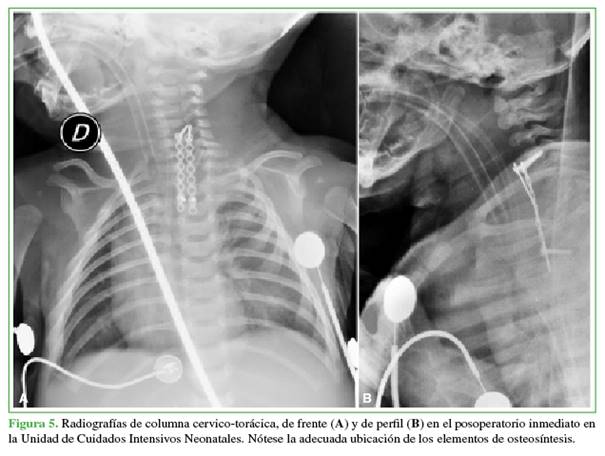

Sin embargo, el uso del monitoreo impidió la remoción de un fragmento de peroné para injerto en tirante, y se debió recurrir, en su lugar, a un injerto de costilla como tirante y como astillas (chips) óseas. Se suplementó con 2 miniplacas de titanio para brindar algo de estabilidad al constructo. El control final con el arco en C fue satisfactorio, así como las radiografías en el posoperatorio inmediato (Figura 5).

La instrumentación cervical y de columna torácica alta en niños, por lo general, no está exenta de complicaciones, sobre todo cuanto más pequeños son los niños.21 Si bien se ha utilizado con éxito en la columna torácica alta en niños <2 años,22 existen pocos reportes exitosos en menores de 1 año,3 y no hemos encontrado comunicaciones de uso de implantes por vía anterior en recién nacidos. En nuestro caso, el agregado de un implante de este tipo brindó mayor seguridad al constructo intraoperatorio (Figura 5) y, aunque hubo un desmontaje parcial (Figura 7), las placas permitieron mantener los injertos en su sitio hasta la consolidación del foco (Figura 8).